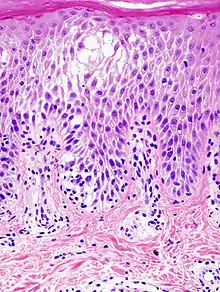

Spongiosis

Spongiosis is mainly intercellular[1] edema (abnormal accumulation of fluid) in the epidermis,[2] and is characteristic of eczematous dermatitis, manifested clinically by intraepidermal vesicles (fluid-containing spaces), "juicy" papules, and/or lichenification.[3] It is a severe case of eczema that affects the epidermis, dermis and/or subcutaneous skin tissues.[4][5] The three types of spongiotic dermatitis are acute, subacute and chronic.[5] A dermatologist can diagnose acute spongiotic dermatitis by examining the skin during an office visit but a biopsy is needed for an accurate diagnosis of the type.[6]